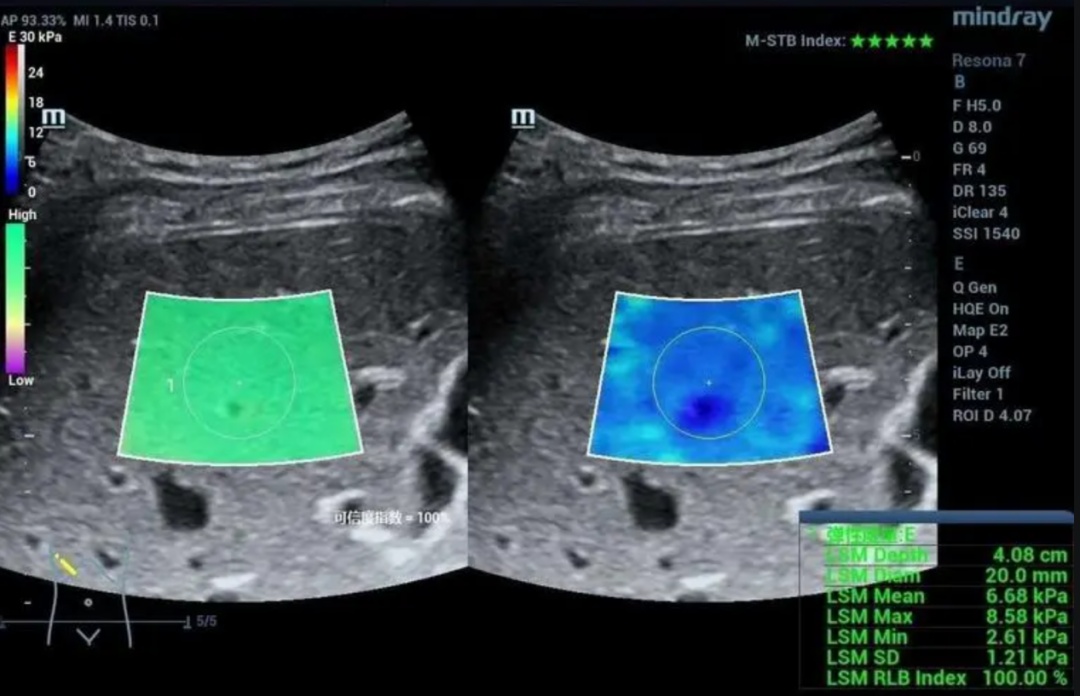

目前,检查肝纤维化更多采用一种无创性评估肝纤维化的新方法:二维实时剪切波超声弹性成像,俗称肝弹,它是用一种超声新技术来检测肝脏的硬度,做一次彩超就可以把肝脏硬不硬给看清楚,同时还能观察肝内有无占位性病灶。

肝脏硬度值正常参考值范围为2.8~7.4kPa。

超过正常值,检测值越高,代表肝纤维化程度越高。对肝弹检测值所反映的肝纤维化程度进行分析时需充分考虑病因及肝功能(ALT、TBil等)指标的影响。

对于慢乙肝患者,通常在谷丙转氨酶(ALT)及总胆红素(TBil)均正常的情况下,LSM 7~8.5 kPa可以确定显著肝纤维化(F2)、排除及确诊肝硬化(F4)的界值为11 ~14 kPa。F2及F4是临床关注的重点,F2是启动抗病毒治疗的重要指标,F4时则需积极治疗及肝癌监测。